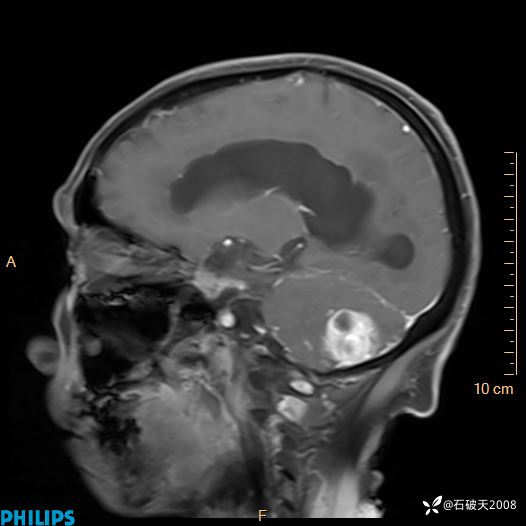

增强矢状位